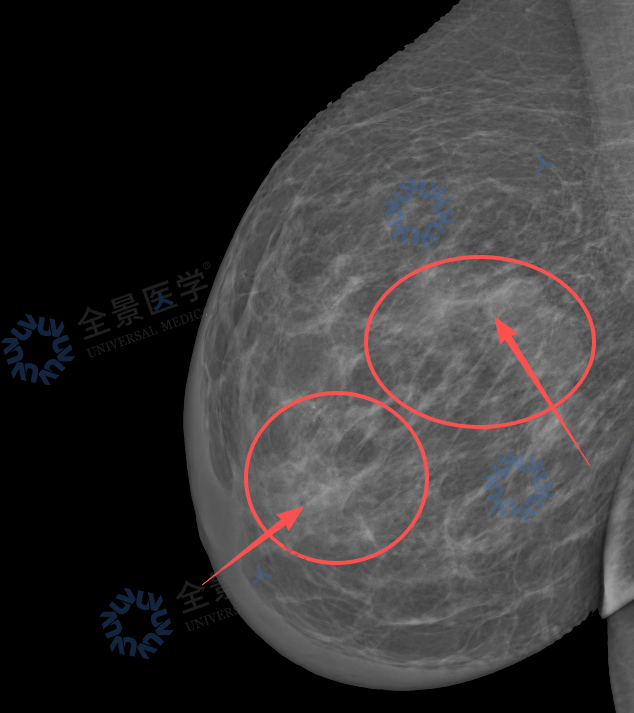

· 钼靶提示右乳多发高密度影伴钙化,BI-RADS 4B~4C;

钼靶: 利用低能 X 线穿透乳腺软组织,靠组织密度差异成像。对 40 岁以上女性友好,擅长发现微小钙化,是早期乳腺癌筛查的「金标准」。